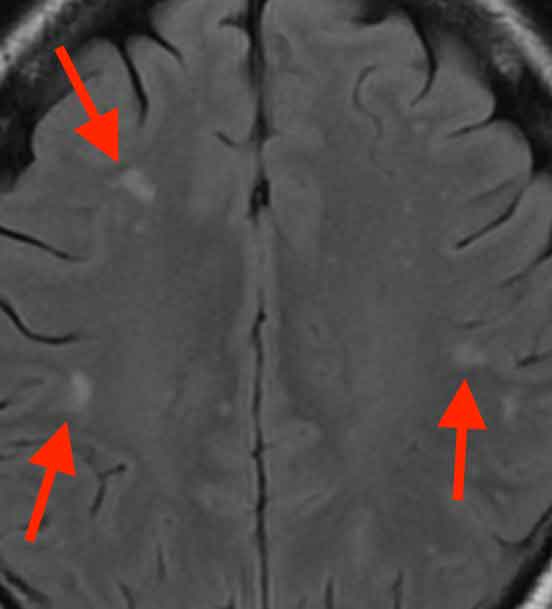

所々に白く写っている部分が見られました。これは白質病変といって、片頭痛の方でしばしば見られる変化です。前医では、これらを「隠れ脳梗塞」と診断したものと思われます。

白く写っている部分が2ヶ所あり、内部が黒く穴があいたように見えます。血管が詰まると、その先の脳細胞に血液が行かなくなり、壊死といって脳細胞は死んでしまいます。その結果、壊死した部分は抜け落ちて空洞になるため、このように写ります。

片頭痛で見られる白質病変と本当の隠れ脳梗塞は、明らかに別のもので画像所見も異なります。前医では、これらを区別できず、白質病変を隠れ脳梗塞と誤診したものと思われます。